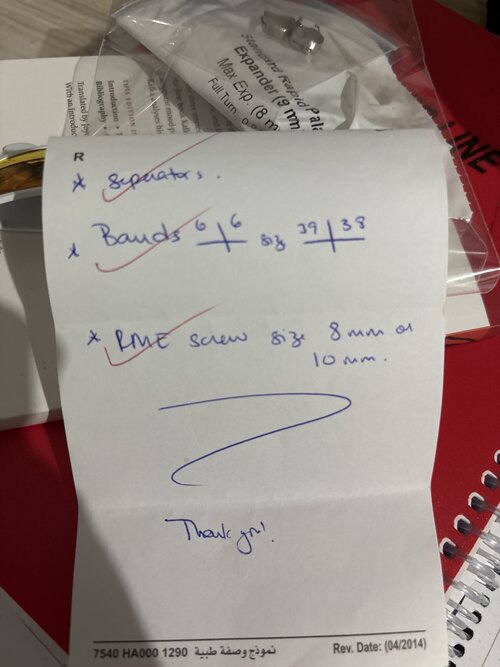

I’m getting a RME on Wednesday recommend by my orthodontist do I need it or will it fuck me up? I heard for some people it went really well and for some it ruined them.

I’m also getting braces with them.